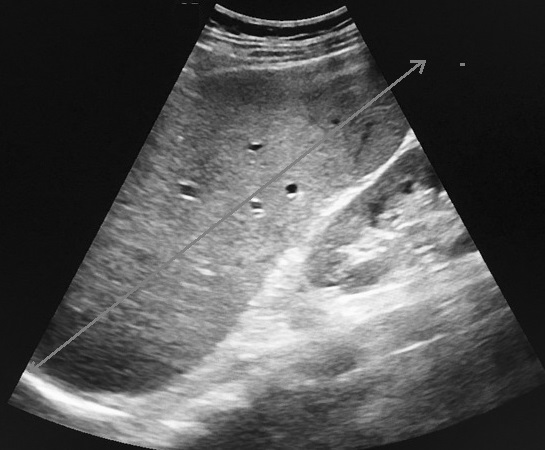

Image

echographique une rate poly-splénique siue au hile

de la rate avec aspect des nodules fragmentees

hilaire hypoechogene . En differentié avec

image arrondie aechogène des vaisseaux hilaires

de la rate . |